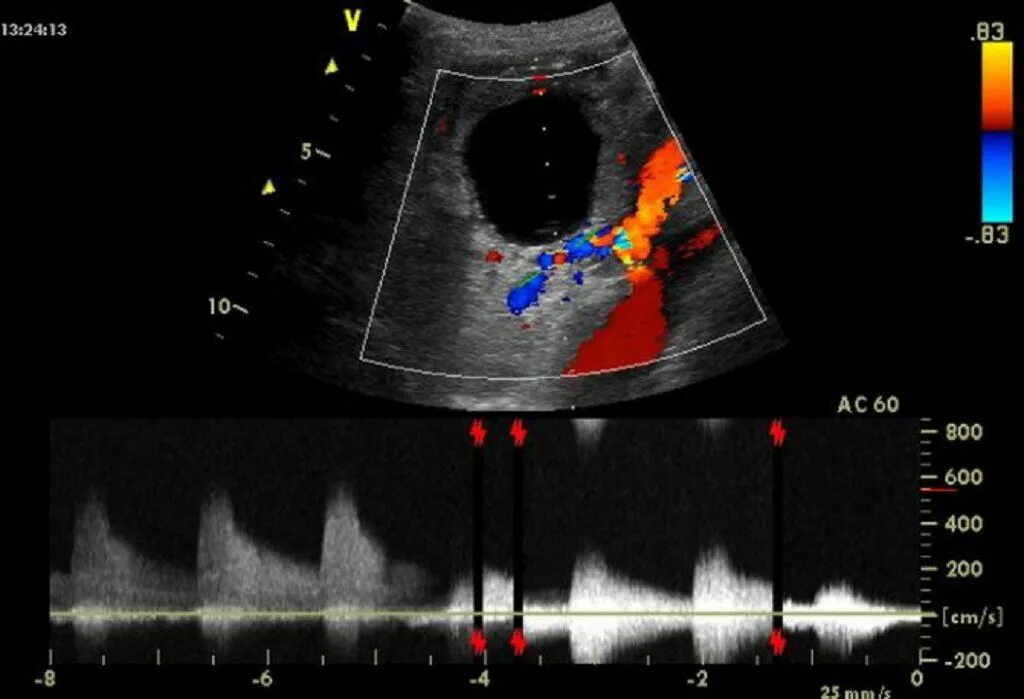

Узи сердца узи почек